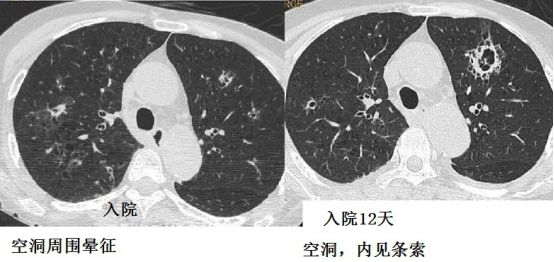

例5:患者免疫力低下,咳嗽咳痰,咯血

图7-8 胸部CT

图7-8 胸部CT肺结核、军团菌、巨细胞病毒、肉芽肿、肺癌等有可能形成晕征,但是结合患者免疫力低下,对曲霉菌的特异性还是很高的。

免疫力低下,实变或者结节周围晕征,要高度怀疑血管侵袭性曲霉病。